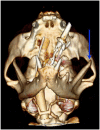

Case series summary: This report summarises and reviews the published cases of open-mouth jaw locking in cats and describes three further cases. Case 1 was a 5-year-old, 5.3 kg male neutered domestic shorthair cat. CT identified changes consistent with temporomandibular joint (TMJ) dysplasia with osseous degenerative changes, and the cat subsequently underwent bilateral partial zygomectomy with bilateral partial coronoidectomy. Case 2 was a 10-year-old, 6.0 kg male neutered Exotic Shorthair. Aside from a fracture of the left maxillary canine tooth crown and absence of the left maxillary fourth premolar tooth, no abnormalities were found on CT scan. The cat also underwent bilateral partial zygomectomy with bilateral partial coronoidectomy. The third case was a 1-year-old, 4.0 kg male neutered Persian cat. Changes on CT were consistent with bilateral TMJ dysplasia, and the cat underwent staged bilateral partial zygomectomy with bilateral partial coronoidectomy. There was no recurrence of open-mouth jaw locking in any of the cases on long-term follow-up.

Relevance and novel information: Open-mouth jaw locking has been reported in cats of a wide range of ages, from 1-10 years. Cats with all skull types (brachycephalic, mesaticephalic and dolichocephalic) may be affected, but brachycephalic breeds seem to be over-represented. A CT scan with the jaw locked in place is recommended for diagnosis and surgical planning purposes; two of the cases reported here document the first cases of TMJ dysplasia in cats to be definitively diagnosed using CT. Trauma and symphyseal or TMJ laxity may also predispose to development of the condition. Partial coronoidectomy and partial zygomatic arch resection performed alone or in combination are generally successful at preventing recurrence. Bilateral partial zygomectomy with bilateral partial coronoidectomy has not previously been reported as a surgical treatment, and is recommended when open-mouth jaw locking occurs bilaterally.